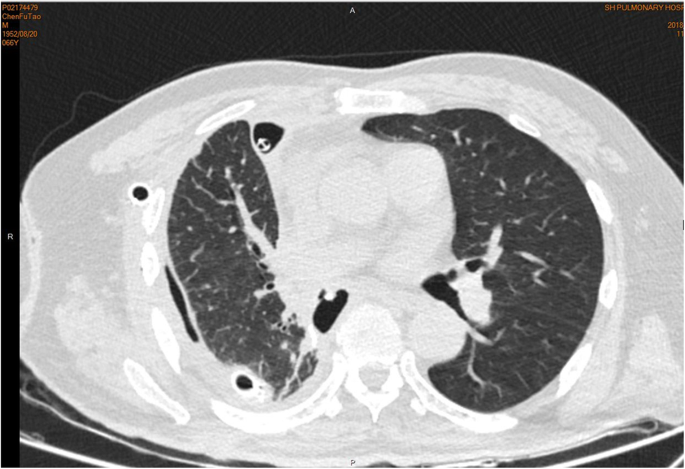

On admission, he had a temperature of 37.0 °C, heart rate of 80 beats per minute, blood pressure of 120/70 mmHg, and an oxygen saturation of 95% on room air. Physical examination revealed no positive sign. Chest CT scan demonstrated a consolidative mass located in the right middle lobe, together with scattered inflammation in the bilateral lower lobes and mediastinal lymphadenopathy (Fig. 1). The patient received ceftriaxone and moxifloxacin intravenously with no improvement. Bronchoscopy exhibited no evidence of tumor or tuberculosis (Fig. 2). Percutaneous lung puncture found inflammatory and tissue cells, and puncture fluid grew Escherichia coli. Pulmonary abscess was diagnosed and the antobiotic was changed to biapenem according to the drug sensitivity result (Table 1). The condition improved and the patient was discharged.

The diagnosis of CBF is not easy clinically because of the complicated pathogenesis and presentations. Since CT scan was widely adopted to observe the pulmonary infection status, it also can be used to visualize the fistula. From the digestive system perspective, flexible colonoscopy is another valuable diagnostic method. A combination of radiological and endoscopic evaluation may obtain a confirmation of CBF. In our patient, CT scan showed an air space near the right rib angle, suspecting the existence of CBF. Meanwhile, sputum culture with positive intestinal flora, such as Escbericbia coli, increased the suspicion of CBF [11]. This was reinforced by the finding of Escbericbia coli in the culture of pulmonary puncture sample.